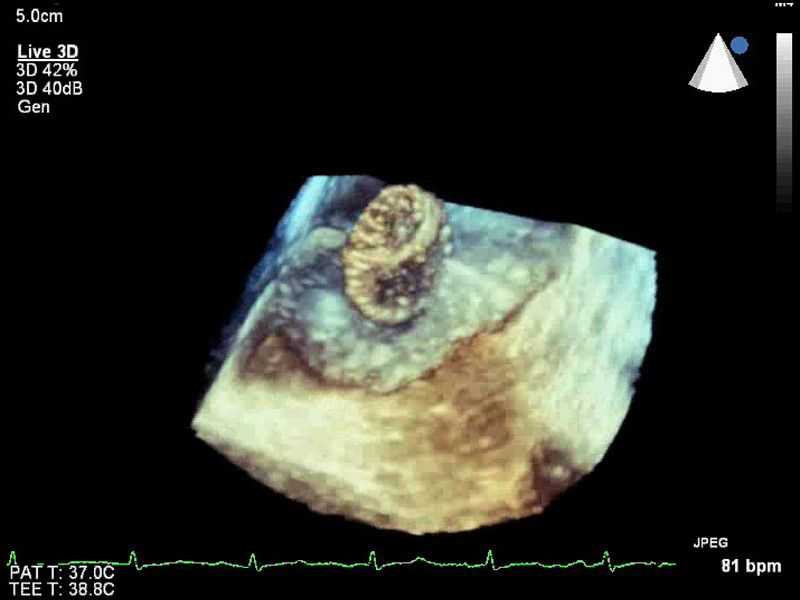

• Live 3D TEE: Эта функция позволяет проводить чреспищеводную эхокардиографию в режиме реального времени, что позволяет оценить механические сокращения сердца с точностью, необходимой для оценки результатов хирургического вмешательства.

• Чреспищеводная эхокардиография